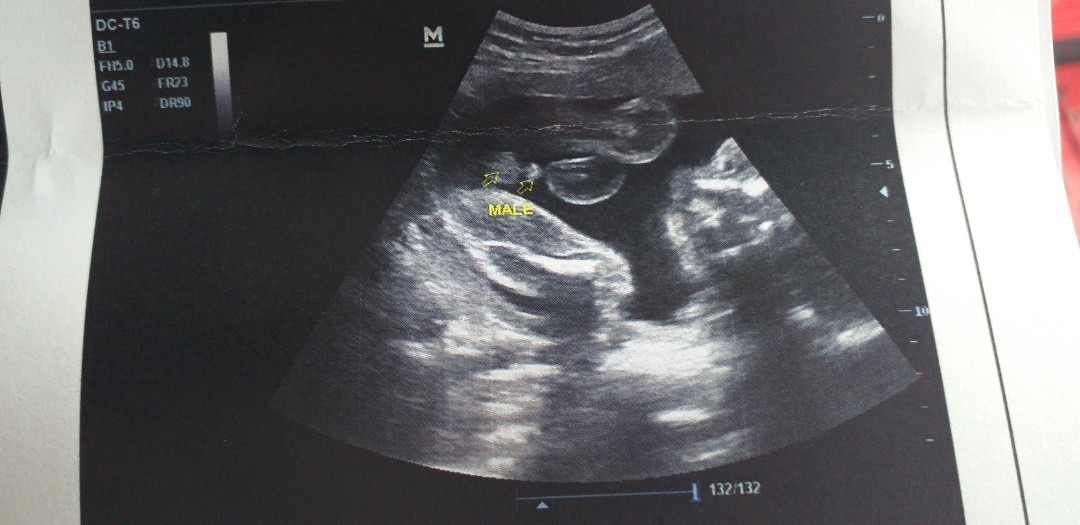

แท่งใหญ่มากจ้า !! 😅

บ้านนี้ได้จู๋จ้า

บ้านนี้มีแท่งจ้า